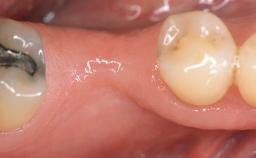

Implant Placement in the Esthetic Zone and Coverage of Multiple Gingival Recessions

This case illustrates use of a modified ‘tunnel’ technique, which has been shown to be highly effective in root coverage procedures. The tunnel technique is used to achieve soft-tissue augmentation across the anterior area, including the planned implant site, using collagen matrix as grafting material. The patient is a 47-year-old woman with high esthetic expectations. Her main concern was the appearance of the anterior teeth and their “elongation”.

Soft Tissue Anatomy Intact Defective